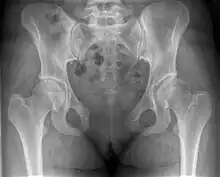

This abnormally wide gap can be diagnosed by radiologic studies such as X-ray, Ultrasound, MRI, CT scan or bone scan. While X-Ray is the gold standard to identify a separation of the pubic symphysis, a decision must be made in regard to which imaging modality to utilize that is patient and case-specific.[3]

Separation of the symphysis pubis (diastasis)

An X-ray film obtained in the AP view of the pelvic inlet and outlet will show a marked gap between the pubic bones.[3] A normal pelvis will show a gap that is 4–5 mm. However, in pregnancy the hormonal influences cause relaxation of the connecting ligaments and the bones separate up to 9 mm. A gap measuring greater than 10 mm indicates a pathological process.[3]

In addition, a view in the "flamingo stance" can be obtained to demonstrate the instability of the joint. This position consists of the patient standing with weight on one leg and the other bent.[6] A vertical displacement of more than 1 cm is an indicator of symphysis pubis instability.[7] A displacement of more than 2 cm usually indicates involvement of the sacroiliac joints.[3]

A limitation of this imaging study is that X-rays induce radiation and should be avoided during pregnancy.[3]